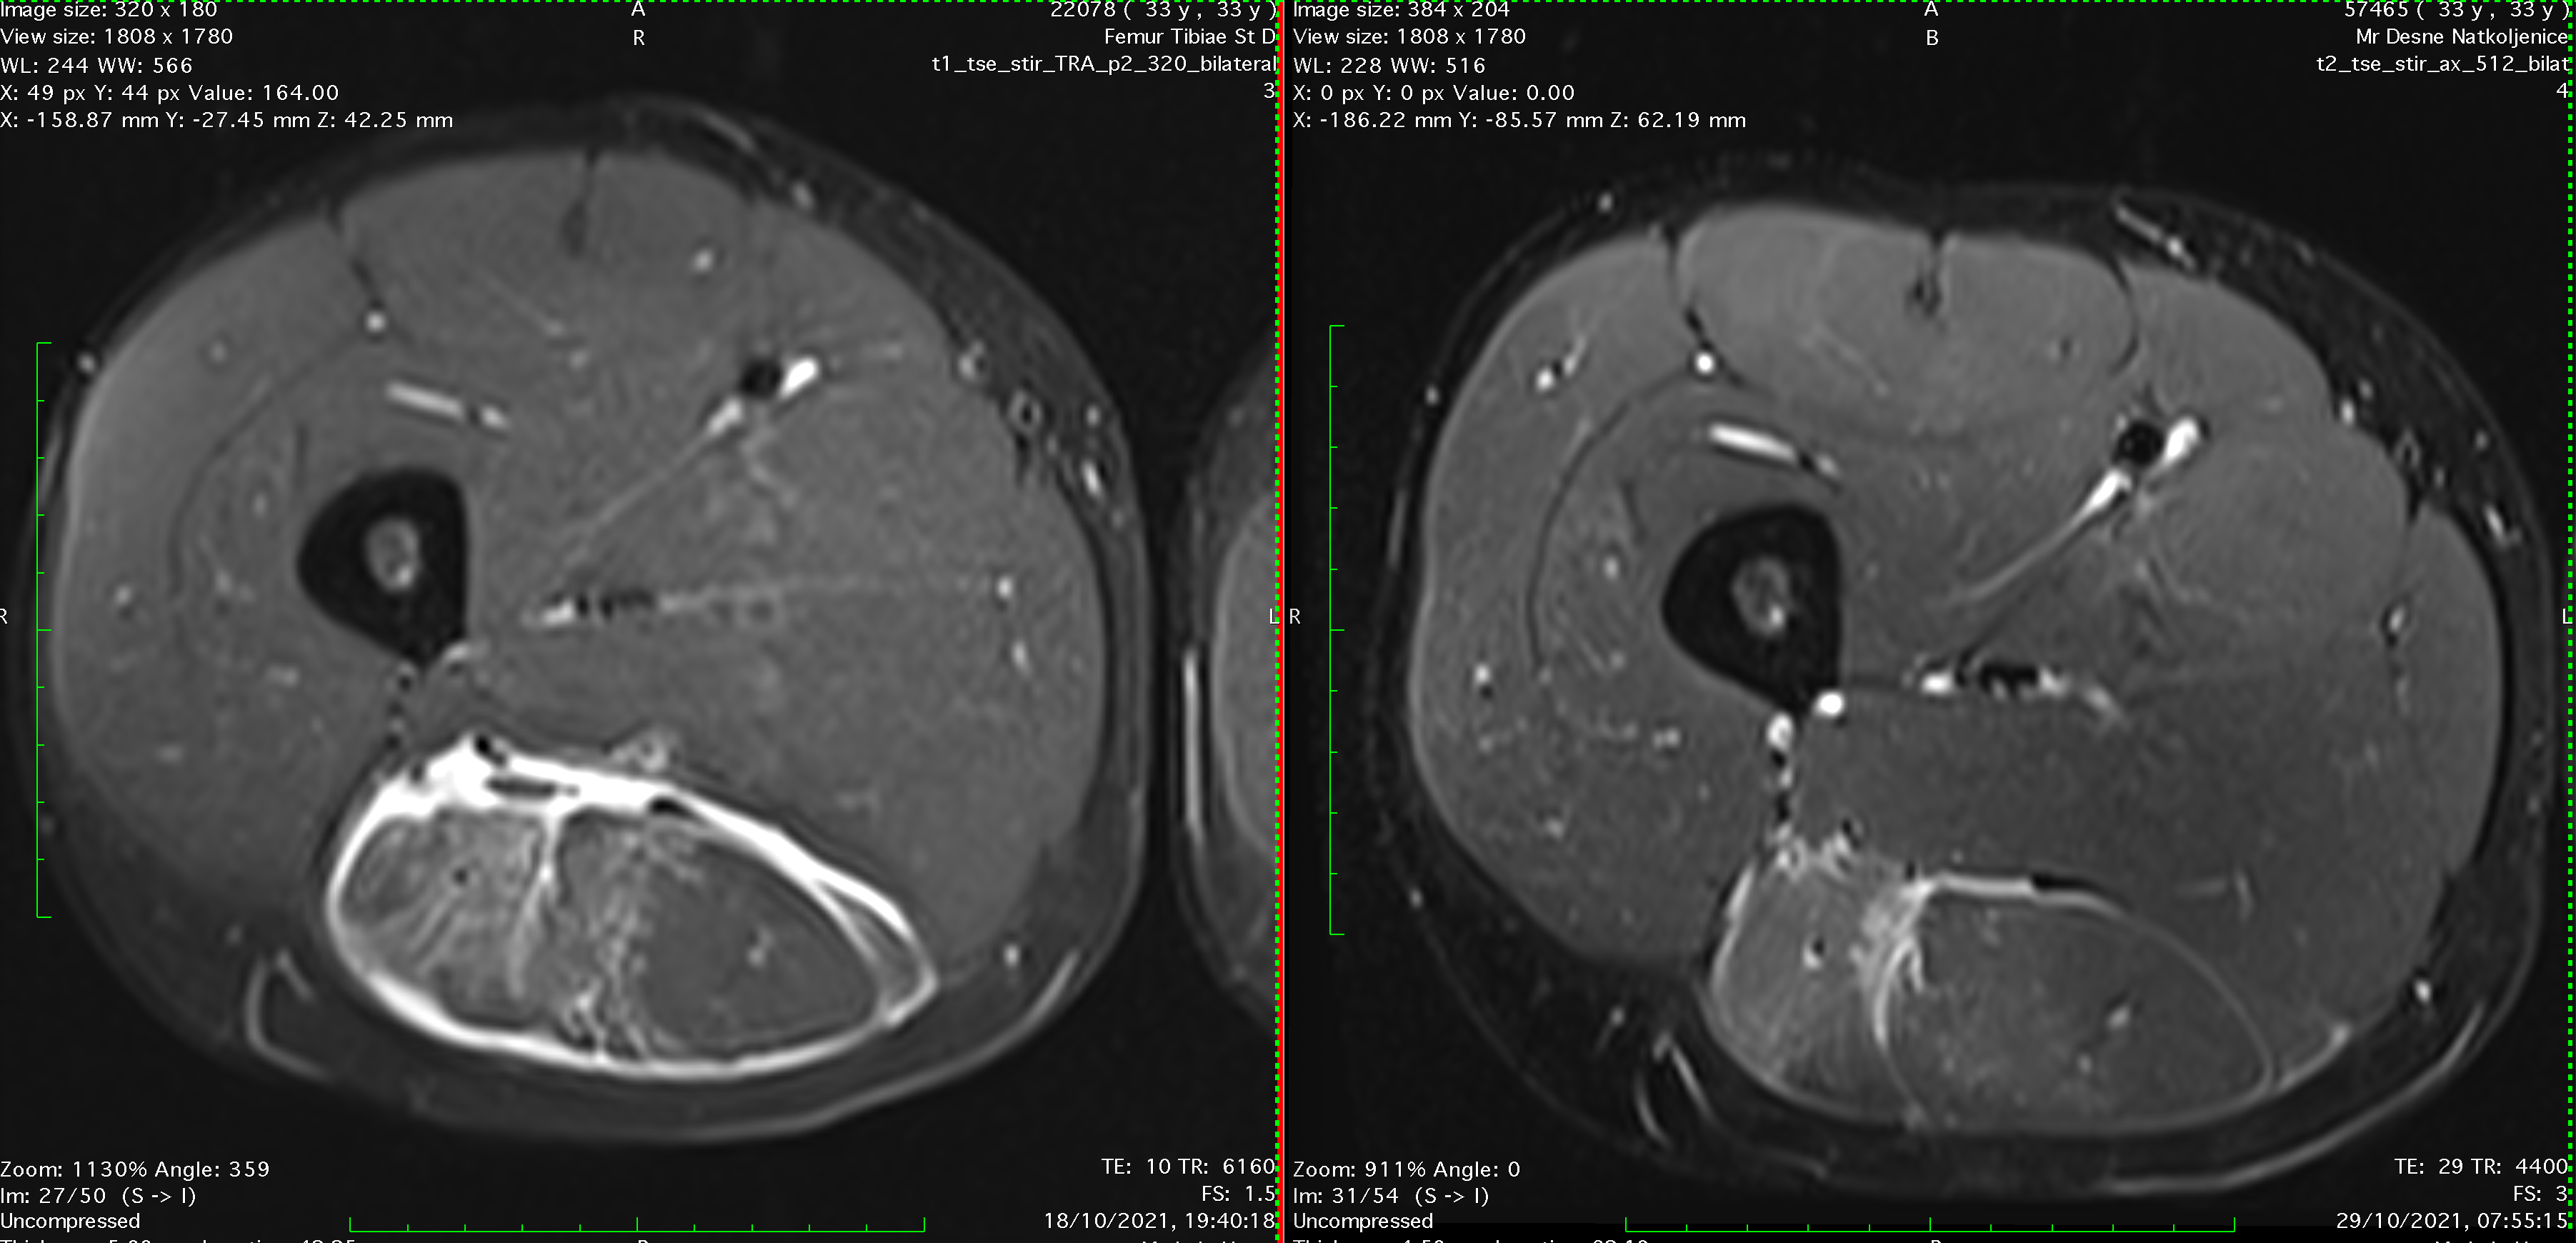

MRI of hamstring intramuscular biceps tendon injury two weeks into the rehabilitation

MRI confirmed a great progress and intramuscular tendon healing! Comparing the two MRIs muscle healed as well and there was no fluid around the muscle.

Comparation of MRIs, left one few days after the injury, right one after first cycle of therapies, two weeks later.